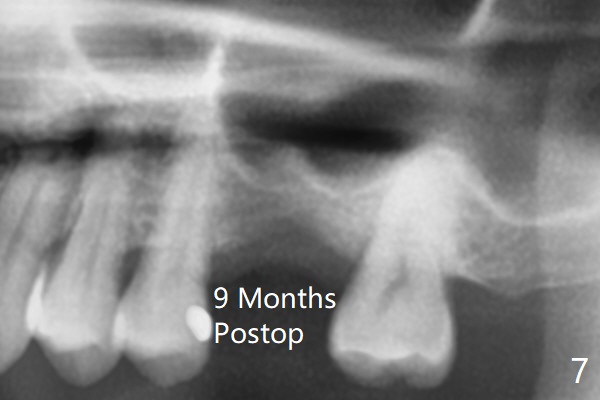

When the crown and abutment at #14 are removed, the implant is found to be shallowly placed. Upon incision, the implant threads are exposed circumferentially and coronal to the buccal crest (Fig.1 *). It seems to be difficult to expect bone regeneration post bone graft. The implant (6.4x6 mm) is removed with a 7/8 mm trephine bur, followed by sticky allograft (Fig.2 *), PRF membrane and 6-month membrane. In spite of the setback, the bone height increases from 3.9 mm to 11 mm due to sinus lift associated with the previous implant placement (Fig.2 L). The depth of the 2nd placement will be controlled by surgical guide. When the periodontal dressing dislodges 11 days postop, the 6-month membrane is lost as well as part of the bone graft. If there is remaining apical native bone, an immediate implant should be placed so that bone graft can be kept in place more securely with an immediate abutment and provisional! The seemingly conservative approach is actually not safe. The wound heals 1 month postop (following dislodgement of the 2nd periodontal dressing, Fig.3). Three months later, consider using bone expanders to do sinus lift and place a SM implant subcrestal. Take PA after 1st expander to the depth. The wound heals 4 months postop (Fig.4), but the bone height (Fig.5) and width (Fig.6) decreases. The latter continues to decrease 9 months postop (Fig.7,8), but bone density is high, average 1360 units. Preparation includes guide, incision, sinus lift, implant placement (possibly tissue-level (9) or FC if the sinus membrane perforates), bone graft, and suture.